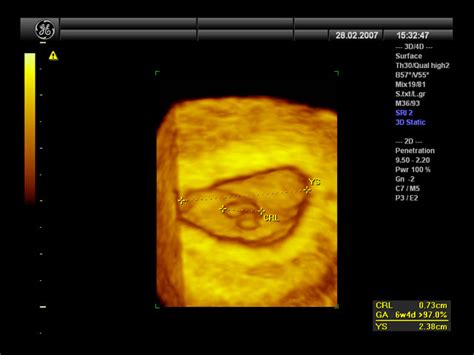

V zgodnji nosečnosti, ko je plod v uviti drži, merjenje njegove dolžine od glave do pet ni mogoče. Namesto tega se izmeri dolžina od glave do zadka (CRL - Crown-Rump Length). CRL meritev je ponovljivo in najbolj natančno merilo gestacijske starosti. Plod od 6. tedna gestacijske starosti raste s hitrostjo približno 1 mm na dan. Na podlagi tega se v zgodnji nosečnosti gestacijska starost lahko določi z izračunom - izmerjeni dolžini plodovega odmeva se prišteje 6 tednov nosečnosti.

Sonogram: 6 weeks pregnant !